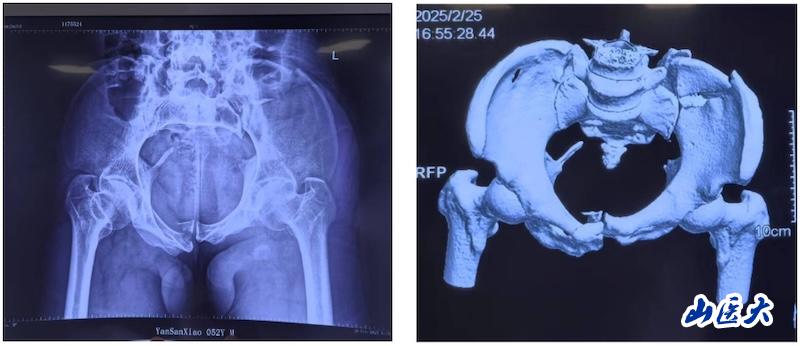

术前

该患者在驾驶三轮车时发生车祸,导致骨盆骨折,经过当地医院对症治疗后转入我校第二医院急诊科。由于血色素持续下降,血管外科首先进行了血管介入栓塞处理,随后转入骨科创伤病区,由孙海钰团队接续治疗。经过详细检查和评估,孙海钰主任、贺冬冬副主任医师、王欢副主任医师为患者制定了运用UCRT解锁复位技术,结合天玑机器人及O-arm术中影像系统为其实施骨盆闭合复位的手术治疗方案。3月6日,孙海钰团队在骨科老一辈专家尹芸生主任的指导及麻醉师、技师、器械护士和巡回护士的通力协助下,成功运用微创新技术为患者实施了手术。

据孙海钰介绍,骨盆髋臼骨折是一种严重的创伤,传统开放复位内固定术创伤大、恢复慢,而闭合复位则具有微创、出血少、恢复快等优点。随着医疗技术的不断进步,UCRT解锁复位技术结合天玑机器人及O-arm术中影像系统为骨盆骨折治疗提供了更加精准、微创的解决方案,该技术代表了当前骨盆骨折治疗的前沿方向。